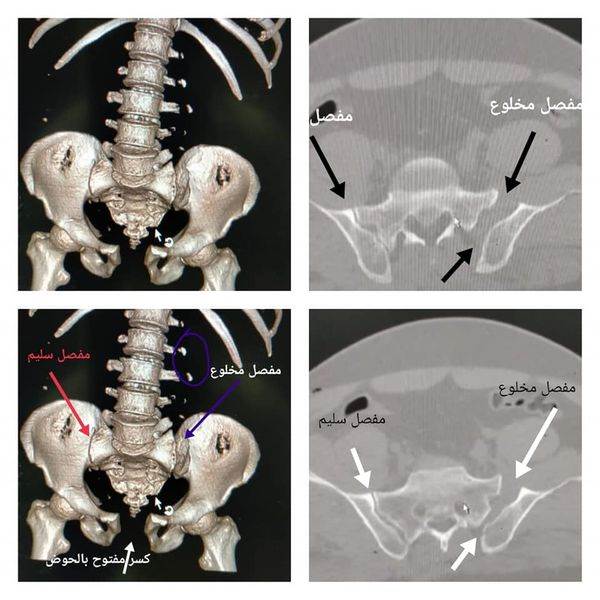

وأعلن الدكتور تامر حمدى مدير إدارة المستشفى، أن المريض تعرض لإصابة شديدة أدت إلى كسر مفتوح وغير مستقر بالحوض من الدرجة الثالثة ( الأخيرة )، مع وجود قصور حاد بالدورة الدموية أدى إلى غيبوبة نتيحة فقدان الدم نتيجة كسر الحوض وجرح متهتك غير نافذ حول فتحة الشرج واصابة بمجرى المسالك البولية، مما استدعى تقديم الإسعافات الأولية للمريض بمجرد وصوله الى المستشفى ونقل الدم والبلازما له، وإجراء جراحة عاجلة لرد وتثبيت كسور الحوض بو اسطة شرائح و مسامير عن طريق فريق جراحة العظام لإيقاف النزيف، وتم عمل استكشاف للبطن والمثانة، وأنه بعد العملية عادت العلامات الحيوية للمريض إلى طبيعتها وحالته أصبحت مستقرة الآن .

وأشار الى أن كسور الحوض، تعد واحدة من أكثر الكسور خطورة، والتي تحدث نتيجة إصابات شديدة مثل حوادث السيارات والسقوط من علو، وتعتبر عمليات جراحة كسور الحوض والحق من أعقد وأدق العمليات الجراحية، وتحتاج الى خبرة ودقة متناهية لتلافى حدوث مضاعفات خطيرة أثناء العملية ، وذلك بسبب وجود شبكة من الأعصاب والشراين والأوردة، ومن أشهر المضاعفات أثناء العملية النزيف الحاد الذي قد يؤدى إلى الوفاة واصابات الأعصاب وجلطات الأوردة والرئة .